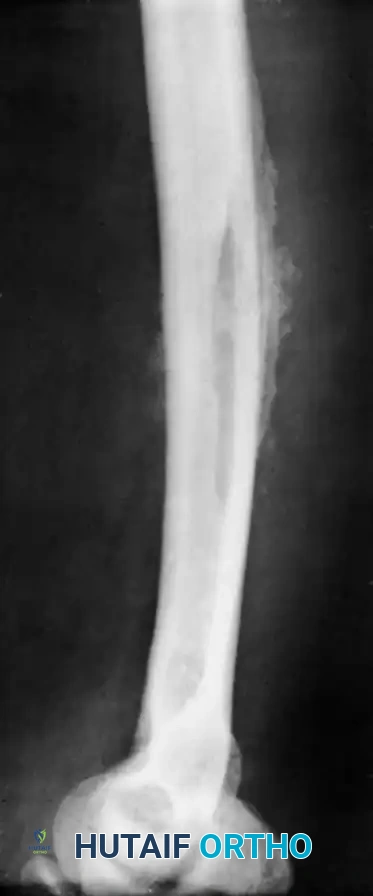

Fig. 16-2 Pathological fracture after destruction of cortical bone by infection. Extensive cortical necrosis and structural compromise can lead to catastrophic mechanical failure if surgical decompression is delayed.

Fig. 16-4 Osteomyelitis of the tibia in a sickle cell patient. Note the extensive diaphyseal involvement characteristic of Salmonella osteomyelitis.